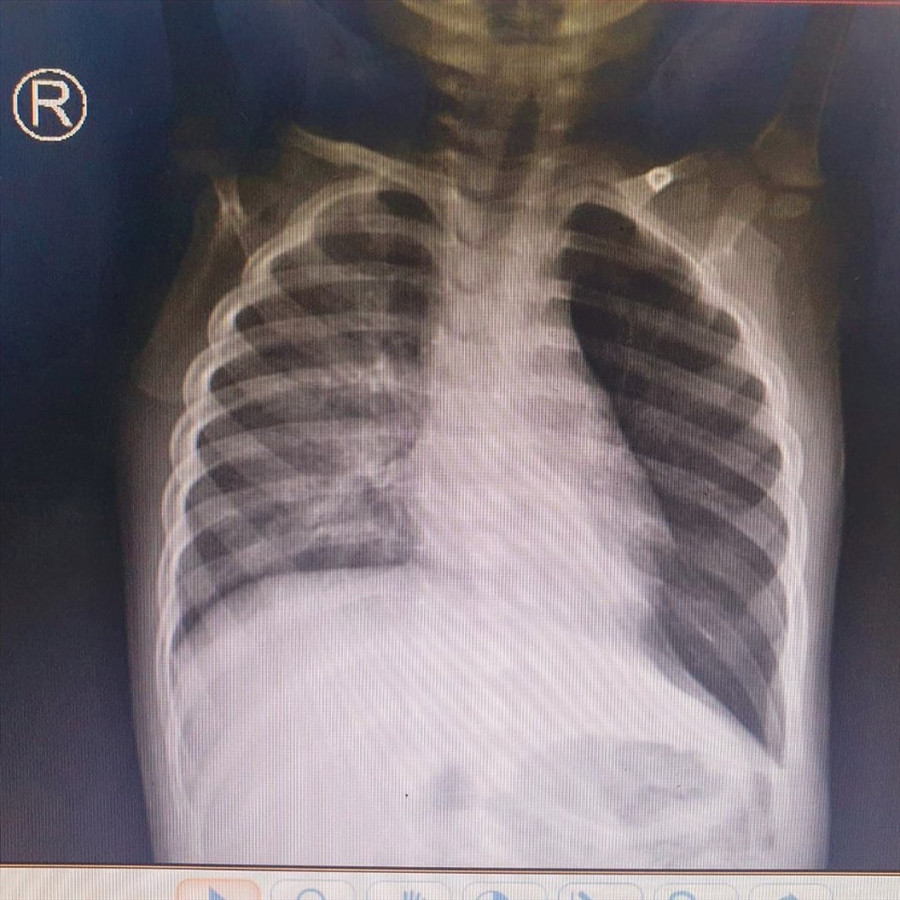

Trẻ được nghi ngờ có dị vật trong đường thở, chụp phim phổi thấy tắc nghẽn hoàn toàn phế quản gốc phổi trái, gây ứ khí phổi trái. Nội soi phế quản cho thấy có dị vật nghi là hạt đậu phộng ở nhánh phế quản gốc trái.